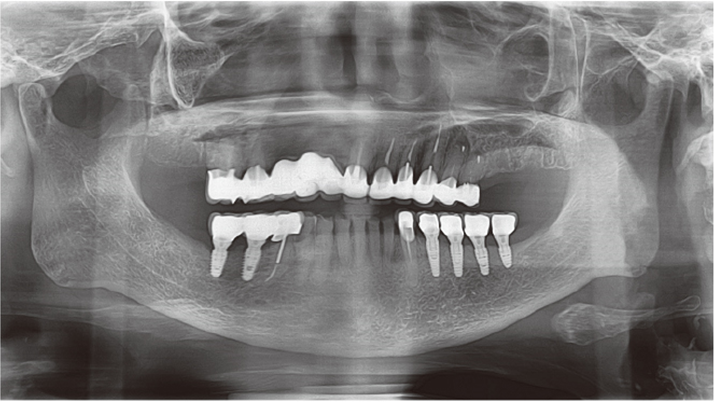

Clinical case: Delayed implant placement: sinus floor elevation by means of lateral

approach & implant placement with GBR

- Courtesy of Dr. Irfan Abas, Netherlands -